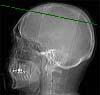

Radioanatomie TDM de l'encéphale avec injection

Sinus sagittal supérieur

Scissure interhémisphèrique